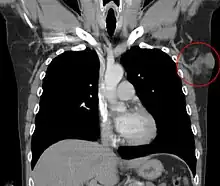

![]() | |

| Histopathological image of dermatofibrosarcoma protuberans. Local recurrence long after the first excision. H&E stain | |